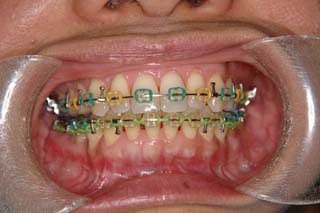

主訴:顎が歪んでいる 下顎が出ている

診断名:骨格性下顎左方偏位を伴う骨格性下顎前突

年齢:28歳

使用した主な装置名:TPB、マルチブラケット装置

抜歯/非抜歯および抜歯部位:抜歯(上顎左右第一小臼歯)

治療期間:動的処置2年3か月、経過観察3年

費用の目安:保険適応 自己負担金として30~50万

リスク、副作用:外科手術によるリスク、マルチブラケット治療に伴う歯根吸収など偶発症が発生するリスクがある。

強い下顎前突と下顎の左方変位がみられます。成長を終了した永久歯列ですので、骨の大きさのズレへのアプローチは大きく別れる所です。程度が小さければ、歯の傾きで補うように解決しますし、大きなズレであれば、外科的に骨のズレを改善する治療が選択されます。前後のズレ、左右のズレと条件が重なってきた場合、より外科矯正での改善が望ましいものとなるでしょう。

一般的な外科矯正治療の流れは、術前矯正・外科矯正・術後矯正・保定治療と移行します。術前矯正では、手術を行う時点で、上下がぴったり合うような歯列に仕上げる事になりますので、逆に言えば、手術をしていない直前においては、とんでもなく噛めない状態となっている事が多いです。このケースでは下顎のみのセットバック(後退術)をSSROにて行いました。